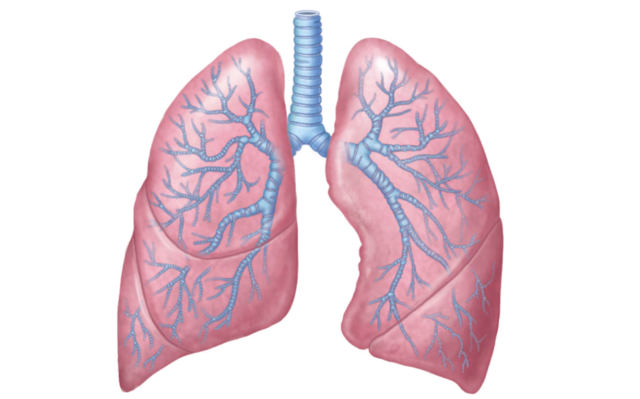

• Week Twenty Four

Week Twenty Four

The fetus's lungs are developing branches of the respiratory tree and cells that produce surfactant. (The image is of a newborn receiving a surfactant treatment)